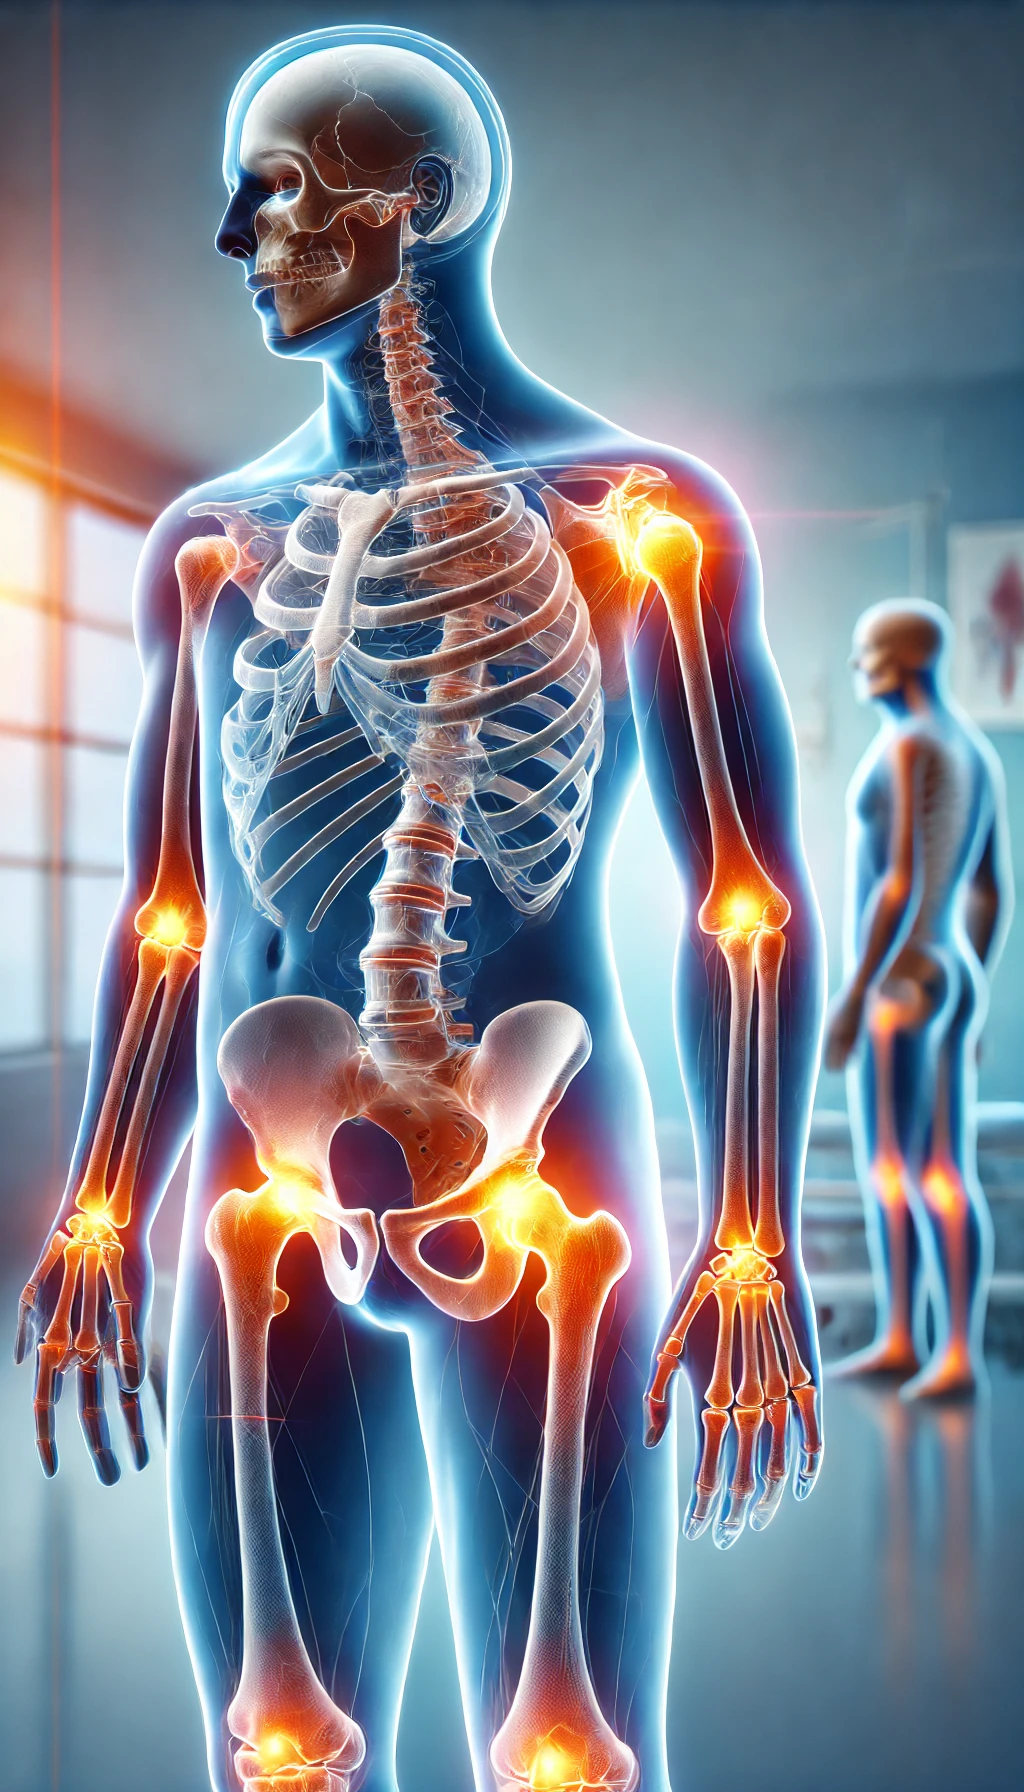

A artrose de joelho é uma das doenças reumáticas mais frequentes e incapacitantes, especialmente após os 50 anos. Trata-se de um processo degenerativo que compromete